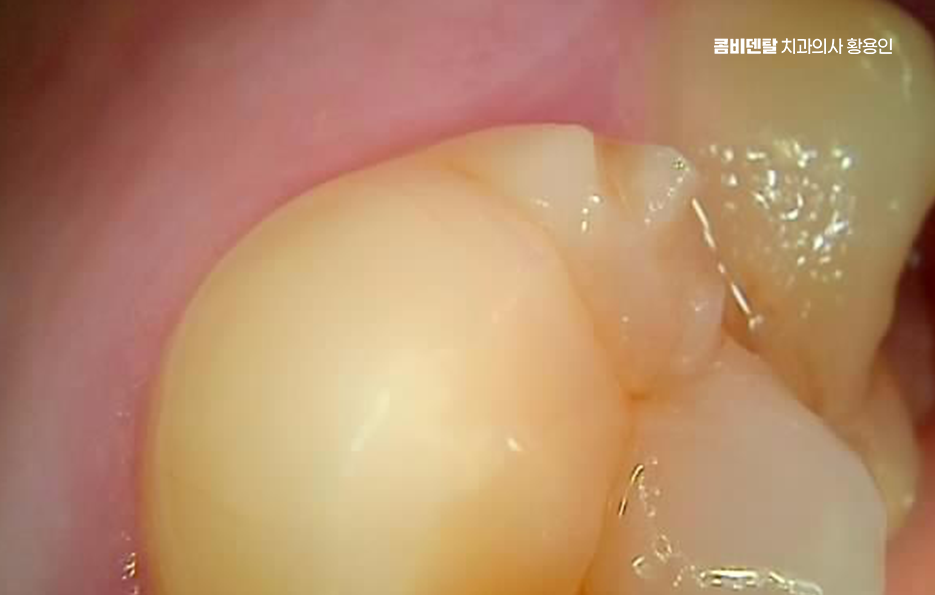

지금과 달리 예전에는 충치 치료라고 하면 거의 아말감으로 떼우는 게 기본이었는데 지금은 소재도, 기술도 발전하면서 상황이 달라졌어요. 하지만 여전히 예전에 치료했던 아말감이 입 안 어딘가에 남아 있는 경우가 많고 겉보기에는 튼튼해 보일 수 있지만, 오래된 아말감은 내부에서 골치 아픈 문제가 자라고 있을 수도 있었어요

처음엔 안 보일 정도의 크랙이 생기고, 그 사이로 음식물과 세균이 침투하면서 2차 충치가 생기기 쉬운 것이며 특히 어금니처럼 씹는 힘이 센 부위에 들어간 아말감은 이런 팽창으로 인해 치아에 미세한 금을 만들고, 결국은 깨지거나 뿌리까지 손상이 가는 일이 생길 수 있기 때문에 늦지 않게 아말감 교체 레진 같은 재료로 재치료를 고려해야 할 수 있었어요